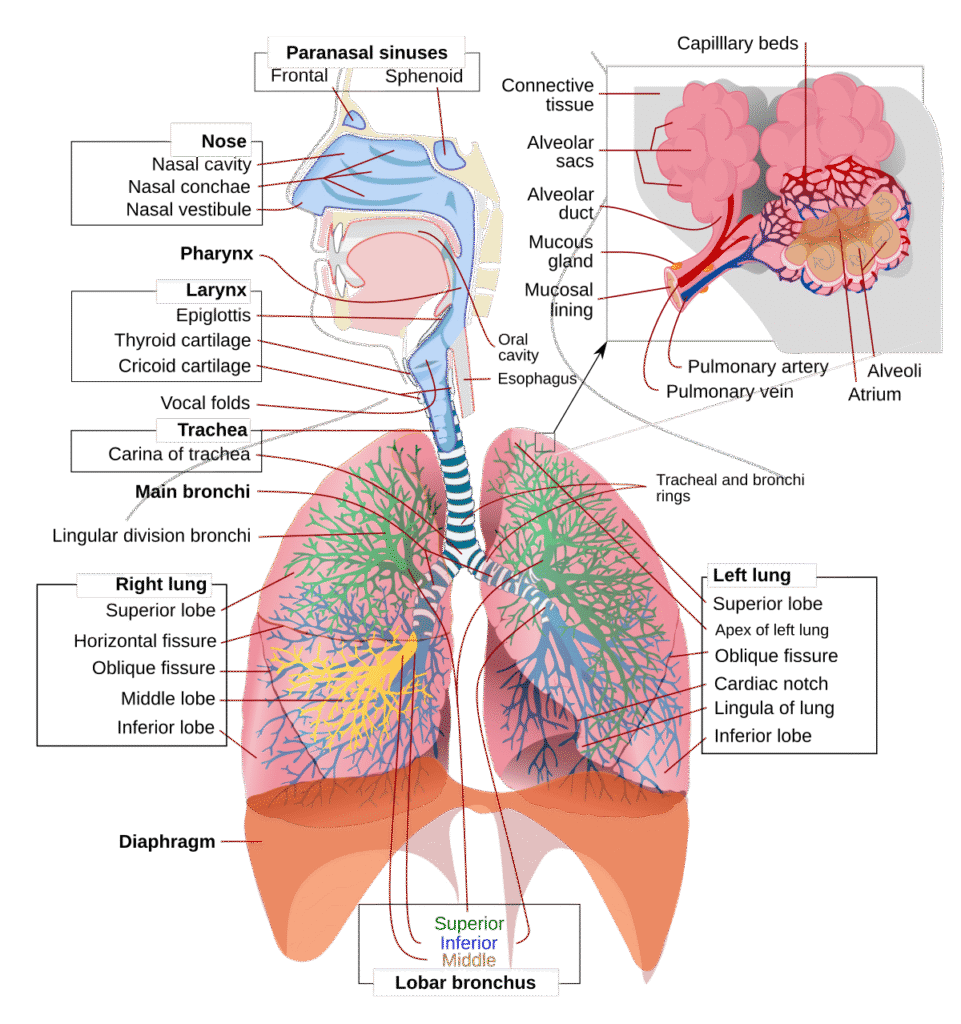

Intubation contraindications can be divided into those Both Nasal and Oral lntubation and those for Nasal Intubation. Both Nasal and Oral lntubation Contraindications • Laryngeal edema. • Epiglottitis. • Laryngotracheobronchitis This is one among the important Intubation Contraindications. In these conditions the airway is already compromised giving very little place for the endotracheal Tube to […]